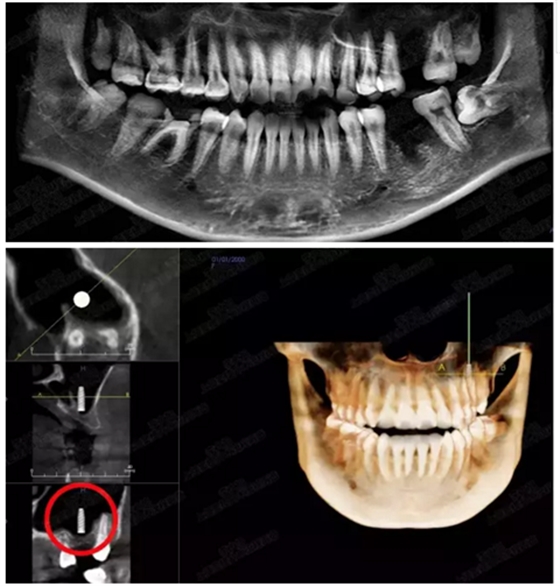

病例三

剩余骨量3mm

005.png

006.png

病例四

剩余骨量2mm-5mm且存在斜形竇底

007.png

提升8mm

008.png

009.png